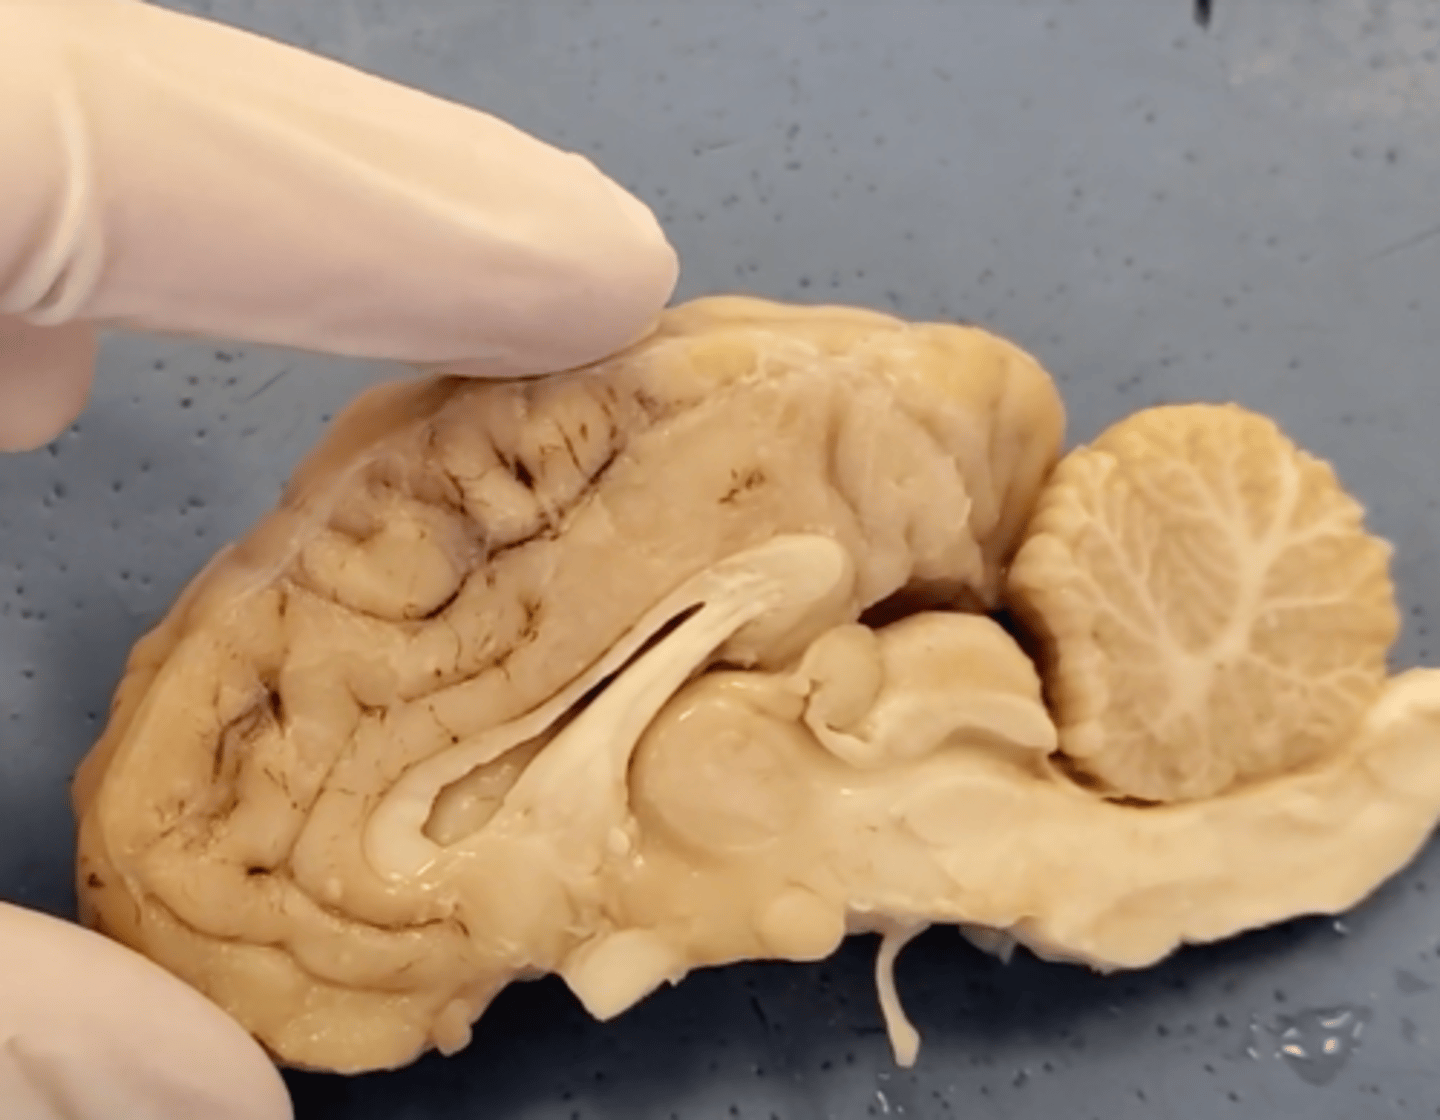

cerebrum

Area of the brain responsible for all voluntary activities of the body

cerebellum

A large structure of the hindbrain that controls fine motor skills.

olfactory bulb

a brain structure located above the nasal cavity beneath the frontal lobes

medula oblongata

part of the brain that controls breathing, heartbeat, and the size of blood vessels

optic chiasma

the crossing of the optic nerves from the two eyes at the base of the brain

optic nerve

the nerve that carries neural impulses from the eye to the brain

corpus callosum

the large band of neural fibers connecting the two brain hemispheres and carrying messages between them